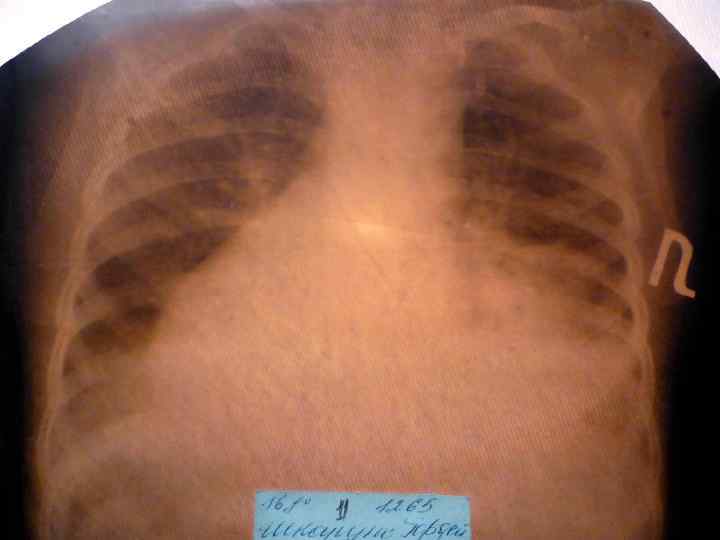

Долевая пневмония характеризуется лобарным пневмоническим инфильтратом. Крупозная ( пневмококковая) пневмония диагностируется прежде всего по клиническим данным. Крупозная пневмония сохраняет свою типичную картину пневмококковой пневмонии: острое начало с характерными клиническими данными, циклическое течение, несклонность к деструкции, гомогенной и лобарной инфильтративной тенью при рентгенологическом исследовании. Вместе с тем, широкое использование антибиотиков способствовало значительному снижению числа крупозных пневмоний у детей. Интерстициальная – редкая форма пневмоний, при которой оказывается поражен прежде всего интерстиций. Как правило, интерстициальная пневмония обусловлена вирусами, пневмоцистами, внутриклеточными микроорганизмами и грибами.

Морфологическую форму пневмонии определяют по клинико – рентгенологическим данным: выделяют очаговую, очагово – сливную, долевую ( крупозную), сегментарную и интерстициальную пневмонии. Очаговая – наиболее распространенная форма. Пневмонические очаги чаще бывают размером 1 см и более. Очагово – сливная – инфильтративные изменения в нескольких сегментах или во всей доле легкого, на фоне которых могут быть видны более плотные участки инфильтрации и/или полости деструкции. Сегментарная – в процесс вовлекается весь сегмент, который, как правило, находится в состоянии гиповентиляции, ателектаза. Морфологическая картина воспаления при очаговых и сегментарных пневмониях связана с первичным инфекционным воспалением в бронхах, что дает основание отнести эти варианты поражения легочной ткани к бронхопневмониям, нередко сопровождающихся бронхообструктивным или бронхообтурационным синдромами. В настоящее время данный тип пневмоний у детей встречается наиболее часто.